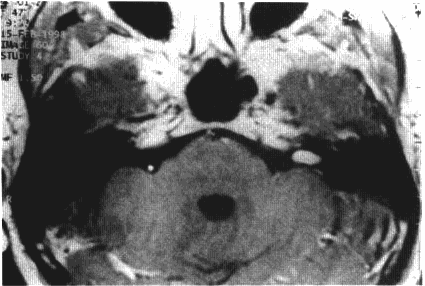

听神经瘤5厘米能手术吗?四种常用的肿瘤分级是Sterkers分类,House分类,Koos分类和Samii分类(见图1),5厘米的听神经瘤属于巨瘤范畴。由听神经瘤引起的症...